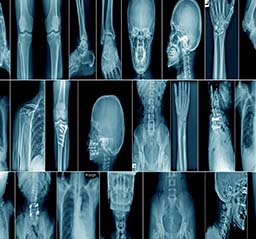

Department of Radiology

Introduction

The radiology department may also be called the X-ray or imaging department. It is the facility in the hospital where radiological examinations of patients are carried out, using the range of equipment listed above.

A radiologist Issues medical imaging such as x-ray, MRI, CT, ultrasound and angiography, to diagnose and treat human disease or injury.

"Departmental Photos"